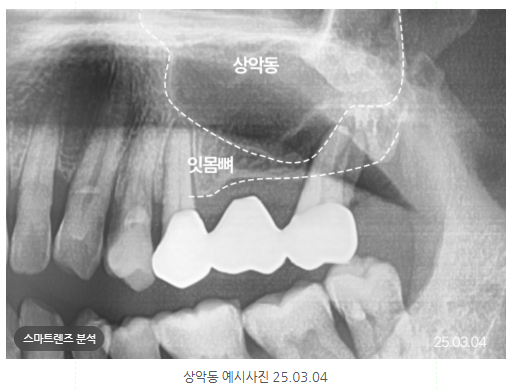

X-ray는 본 칼럼의 이해를 돕기 위해

본.원에서 진료한 동일인의 이미지를

첨부하였습니다.

동의 후 동일 조건에서 촬영하였으며

개인 구강상태에 따라 치.료결과가 달라질 수 있고

상악동 위치

상악동은 코 옆에 있는

광대 안쪽 빈 공간을 말하는데요.

위턱 어금니 뿌리 끝과 근접하여

임플란트 수술과 관련이 있습니다.